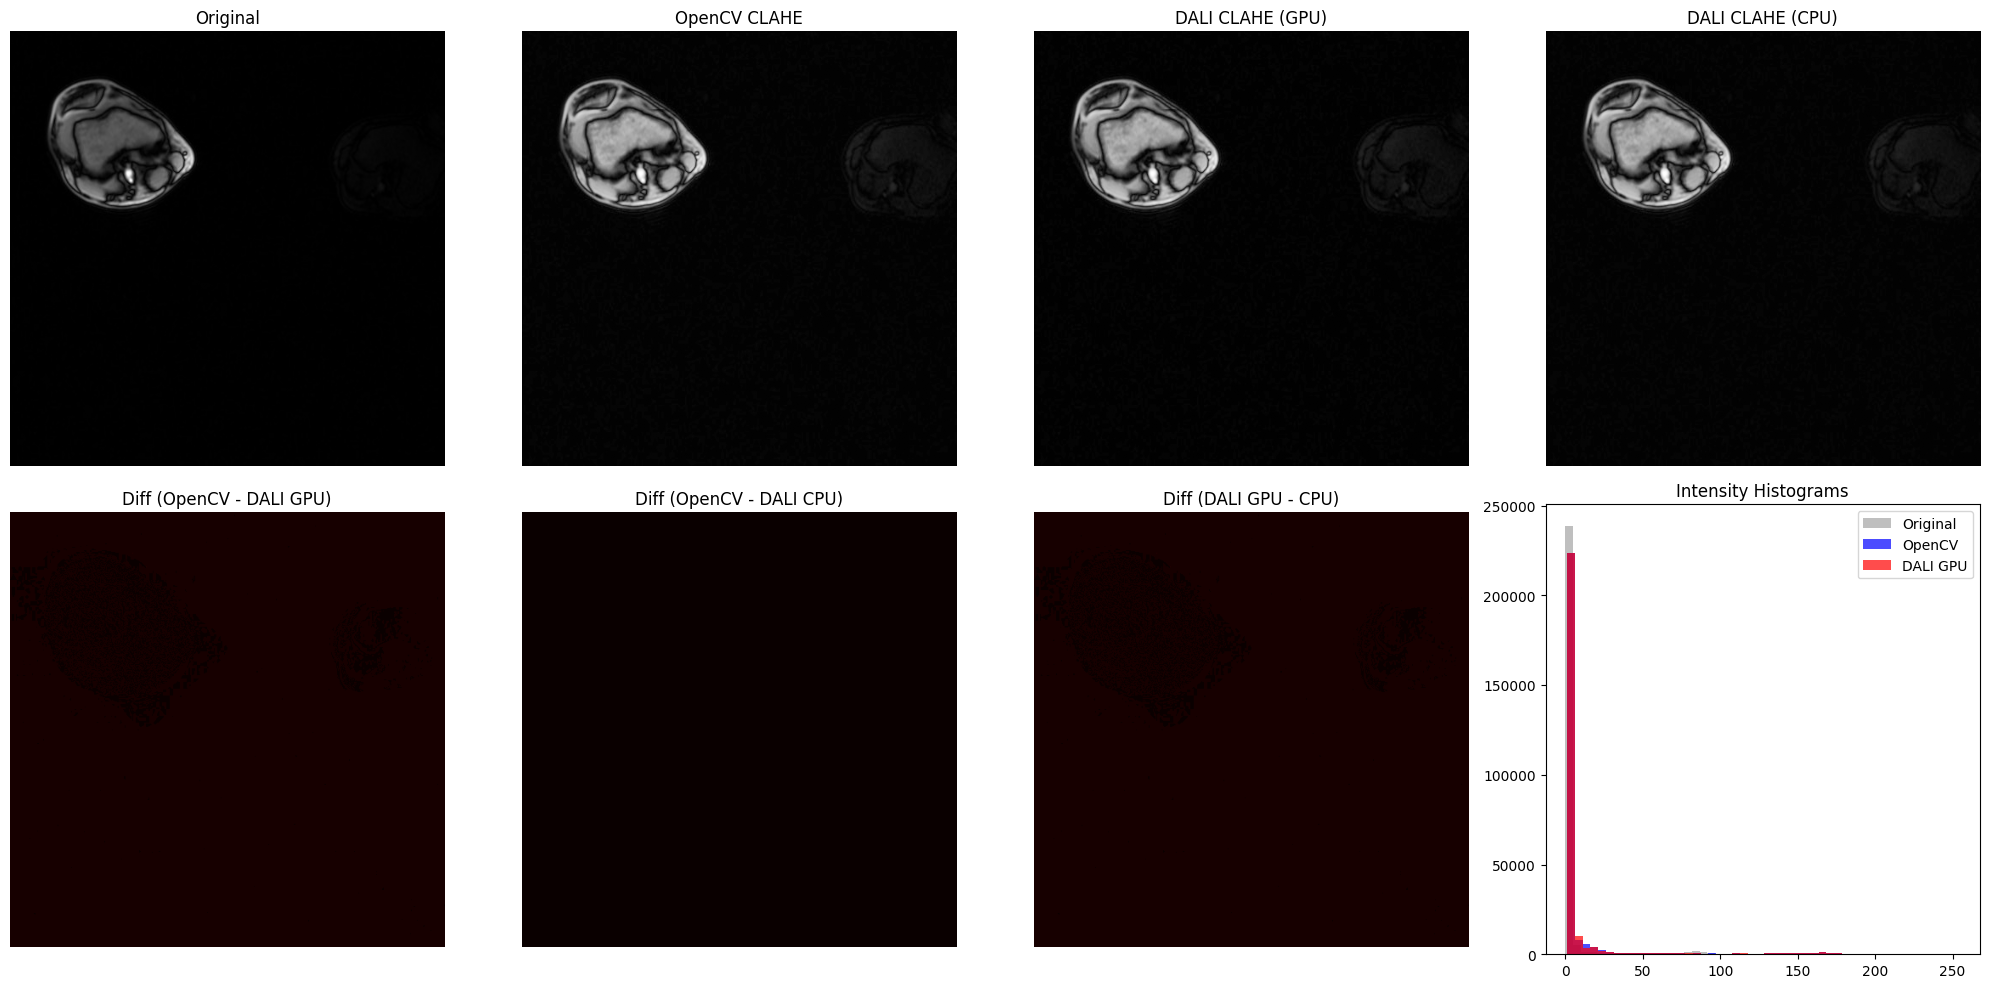

DALI CLAHE vs OpenCV CLAHE on Medical Imaging (Knee MRI)#

This section demonstrates CLAHE on real low-contrast medical imaging data - knee MRI slices from the DALI_extra repository. Medical imaging is where CLAHE truly shines, as these images often have naturally low contrast that benefits significantly from adaptive histogram equalization.

print("\nImplementation Comparison Metrics:")

print("=" * 60)

print(f"OpenCV vs DALI GPU:  MSE = {mse_ocv_gpu:.4f}, MAE = {mae_ocv_gpu:.4f}")

print(f"OpenCV vs DALI CPU:  MSE = {mse_ocv_cpu:.4f}, MAE = {mae_ocv_cpu:.4f}")

print(f"DALI GPU vs CPU:     MSE = {mse_gpu_cpu:.4f}, MAE = {mae_gpu_cpu:.4f}")

print("\nNote: Lower values indicate closer agreement between implementations.")

../../../_images/examples_image_processing_clahe_dynamic_mode_11_0.png

Implementation Comparison Metrics:

============================================================

OpenCV vs DALI GPU:  MSE = 0.9326, MAE = 0.9325

OpenCV vs DALI CPU:  MSE = 0.0000, MAE = 0.0000

DALI GPU vs CPU:     MSE = 0.9326, MAE = 0.9325

Note: Lower values indicate closer agreement between implementations.

[7]:

# Difference Maps and Intensity Histograms

diff_opencv_dali_gpu = np.abs(

opencv_result.astype(float) - dali_gpu_np.astype(float)

)

diff_opencv_dali_cpu = np.abs(

opencv_result.astype(float) - dali_cpu_np.astype(float)

diff_dali_gpu_cpu = np.abs(

dali_gpu_np.astype(float) - dali_cpu_np.astype(float)

fig, axes = plt.subplots(2, 4, figsize=(20, 10))

# Top row: images

axes[0, 0].imshow(mri_array.squeeze(), cmap="gray")

axes[0, 0].set_title("Original")

axes[0, 0].axis("off")

axes[0, 1].imshow(opencv_result.squeeze(), cmap="gray")

axes[0, 1].set_title("OpenCV CLAHE")

axes[0, 1].axis("off")

axes[0, 2].imshow(dali_gpu_flat, cmap="gray")

axes[0, 2].set_title("DALI CLAHE (GPU)")

axes[0, 2].axis("off")

axes[0, 3].imshow(dali_cpu_flat, cmap="gray")

axes[0, 3].set_title("DALI CLAHE (CPU)")

axes[0, 3].axis("off")

# Bottom row: difference maps and histogram

axes[1, 0].imshow(diff_opencv_dali_gpu.squeeze(), cmap="hot", vmin=0, vmax=50)

axes[1, 0].set_title("Diff (OpenCV - DALI GPU)")

axes[1, 0].axis("off")

axes[1, 1].imshow(diff_opencv_dali_cpu.squeeze(), cmap="hot", vmin=0, vmax=50)

axes[1, 1].set_title("Diff (OpenCV - DALI CPU)")

axes[1, 1].axis("off")

axes[1, 2].imshow(diff_dali_gpu_cpu.squeeze(), cmap="hot", vmin=0, vmax=50)

axes[1, 2].set_title("Diff (DALI GPU - CPU)")

axes[1, 2].axis("off")

# Intensity histograms

axes[1, 3].hist(

mri_array.ravel(), bins=50, alpha=0.5, color="gray", label="Original"

opencv_result.ravel(), bins=50, alpha=0.7, color="blue", label="OpenCV"

dali_gpu_np.ravel(), bins=50, alpha=0.7, color="red", label="DALI GPU"

axes[1, 3].set_title("Intensity Histograms")

axes[1, 3].legend()

plt.tight_layout()

../../../_images/examples_image_processing_clahe_dynamic_mode_12_0.png